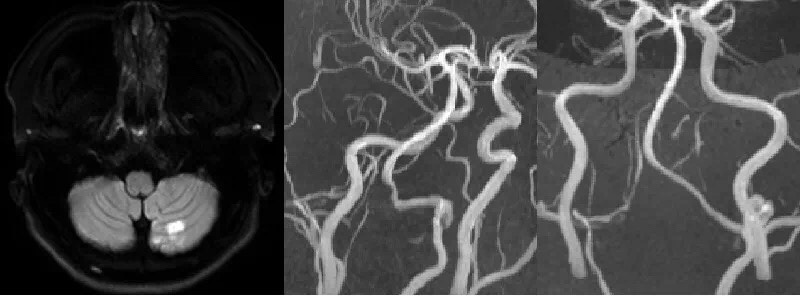

近日,一名27岁的年轻女性因为头痛、眩晕在外院诊治无效,转来惠州市中心人民医院就医,行MRI检查后发现,她的左侧小脑半球有急性脑梗塞。

为什么这么年轻,也没有相关的脑血管病危险因素,就发生缺血性卒中呢?该院为其做头颈部CTA检查发现:左椎动脉V3段局部瘤样扩张,并且从V3-V4段管腔狭窄不一,而右椎动脉很纤细,不知是不是先天发育不良。然而,发生梗塞的原因还是不能明确。

据介绍,常规脑血管成像技术包括MRA、CTA、DSA,只能显示血管轮廓,提示管腔异常的结果,无法明确血管壁病变和挖掘原因。